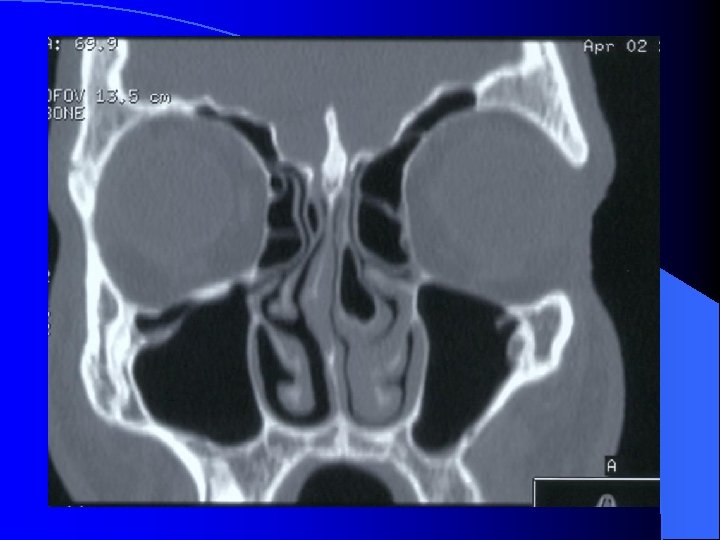

Forme extériorisée = TDM

MALADIES INFECTIEUSES RHINO SINUSIENNES ETHMOIDITE AIGUË IMAGERIE • Radiographie standard • Echo doppler couleur (opérateur dépendant) • TDM sans et avec injection siège, stade collecté, analyse orbitaire fine